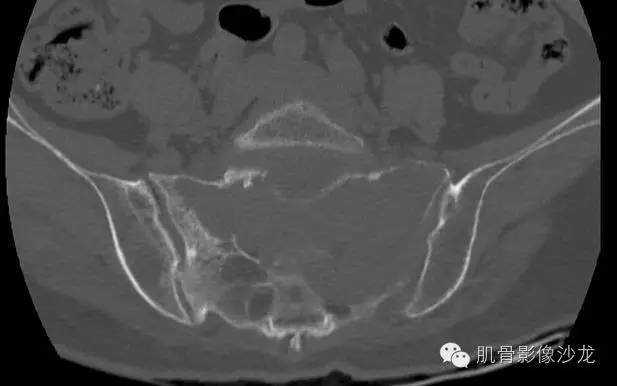

女,50岁,腰痛伴左下肢放射痛4个月

骶骨巨大骨质破坏区,破坏区软组织肿块密度较均匀,边缘不规则残留少许骨皮质,膨胀性改变不明显,肿块基本局限于骨破坏区内。

最后病理:高分化浆细胞瘤

这个溶骨性骨质破坏征象,骶骨的形态还是保留的 所以影像也像浆细胞瘤 但是 转移瘤必须鉴别 转移瘤万能的模仿者

@王斌常德二院 不一定是硬化,有些是残存皮质,这例边缘髓样破坏很明显

有残留骨皮质

没看到到,高密度区都位于皮质或小关节区